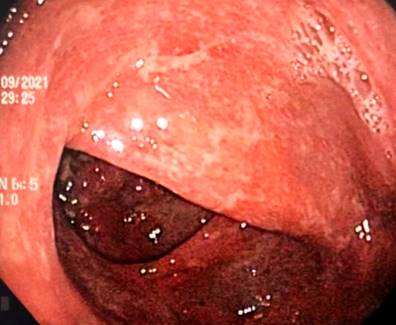

Se trata de una paciente femenina de 43 años con antecedente de EA desde los 20 años (tratamiento previo con etanercept, adalimumab, abatacept y desde 2017 secukinumab), fibromialgia, hipertensión arterial, hipotiroidismo y tuberculosis latente tratada en 2019, quien consultó por clínica de una semana de evolución caracterizada por dolor abdominal difuso asociado a deposiciones diarreicas sanguinolentas múltiples (más de 15 al día). Al ingreso estaba taquicárdica, deshidratada, afebril y con dolor de predominio en el hemiabdomen inferior sin signos de irritación peritoneal. Se realizaron laboratorios en los que el hemograma resultó sin alteración de las líneas celulares, y el estudio ecográfico y tomográfico informaron engrosamiento mural de las paredes del colon derecho con realce mucoso, adenopatías mesentéricas múltiples y escaso líquido libre en el fondo del saco (Figura 1). Se realizó una colonoscopia en la que se encontró edema, eritema, friabilidad de la mucosa, pérdida del patrón vascular y ulceraciones cubiertas por fibrina desde el recto hasta el ciego, hallazgos compatibles con colitis ulcerativa extensa (Figura 2).

Figura 1 Hallazgos tomográficos. Engrosamiento de las paredes del colon ascendente con realce mucoso (flecha). Fuente: archivo de los autores.